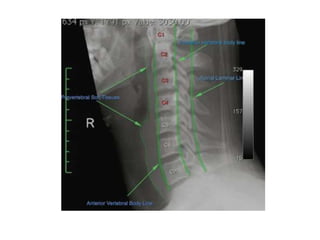

Radiographic Signs ofTrauma Alignment disrupted cervical arcs Focal kyphosis/scoliosis/loss of lordosis Spinous process rotation Vertebral listhesis Cartilage (joint/disc) space facet widening Interspinous widening (ā€œfanningā€) Widened predental space Widened/narrowed disc space

• 12.

Bone Integrity fracture/cortical buckling Disruptedposterior vertebral body line Anterior wedging Disrupted C2 ring (ā€œfatā€ C2 sign) Soft Tissue widened prevertebral space Displaced prevertebral ā€œfatā€ strip Vacuum disc phenomenon Deviated airway

Radiological Assessment • Cervical–X- Ray Lateral A-P especially (( Odontoid # type 2 )) Open mouth • CT thin cuts with reconstruction ( sagittal, Coronal ) • MRI